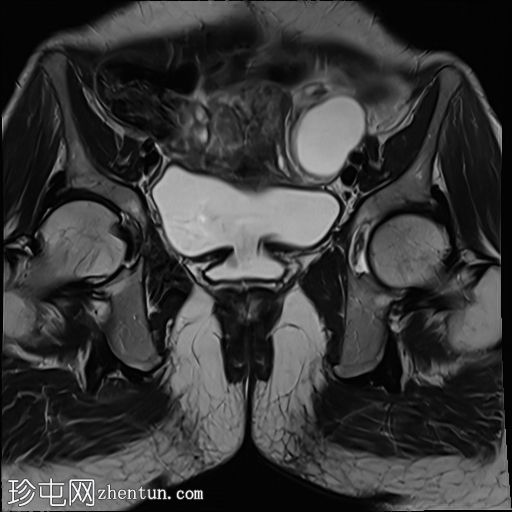

轴位

T2加权像

膀胱后壁与阴道前壁之间存在宽阔的瘘管。膀胱内可见气液平面。

阴道后穹窿上部与直肠中段前壁之间可见另一条较小的瘘管。在重扫描T2加权像上也可见。

此外,还有一个较小的直肠阴道瘘,容易被忽略,但直肠扩张并伴有液体信号强度(未注射凝胶)提示存在直肠阴道瘘。给予患者饮水以充盈膀胱,薄层扫描清晰地显示了狭窄的瘘管。

当膀胱未完全充盈时,直肠阴道瘘不明显,直肠内液体量也很少。然而,膀胱充分充盈后,直肠扩张,瘘管清晰可见。这凸显了在怀疑存在短瘘时,通过注入外源性液体或增加口服液体摄入量等方法确保操作技术正确的重要性,正如本病例所示。